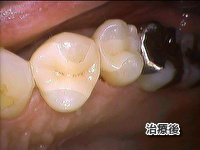

治療例 No.221

左上の歯と歯の間から虫歯になってきましたのでジルコニアのインレーにて治療しました。費用は1本7万円+税で2回で終了しました。

治療前後の写真